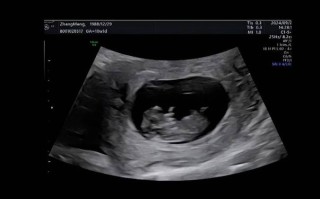

孕期50天B超显示蝌蚪状,是正常胚胎发育还是异常情况?